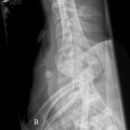

Wirbelsäule Ganzaufnahme seitlich

Es wurden keine Bilder gefunden.

Kassette/Abstand

Format 3 x 35/43 im Ganzbein- WSstativ oder 30/120 Rasterkassette / FFA 3m

Lagerung

Patient steht aufrecht mit der Seite am Rasterwandstativ, Kopf in Neutralstellung, Arme nach vorne ausstrecken und in den Händen kreuzen damit die Schulterblätter rausgezogen werden.

Zentralstrahl

Senkrecht auf Wirbelsäule. Aufblendung von Oberlippe bis einschließlich Hüftköpfe.

Qualitätskriterien

HWS-BWS-LWS mit Sakrum sollte vollständig und gut beurteilbar abgebildet sein.

Indikation

Beurteilung der Wirbelsäulestatik, Kyphose und Skoliose.

Anmerkung

Spezialstativ mit Raster oder Digitalaufnahme mit Abbildung eines Rasters zur Vermessung. Evtl Ausgleichschuhe ausziehen und auch ggf. Verlaufsfilter für guten Kontrast verwenden.